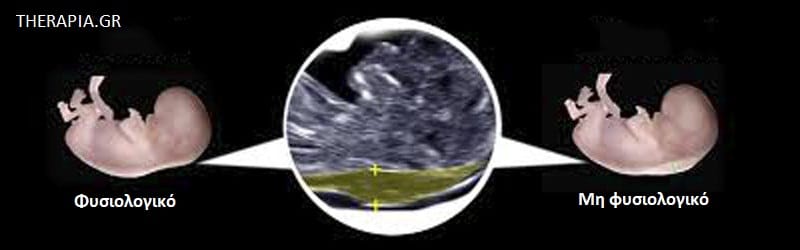

Μπορείτε να δείτε αυτό το υγρό στο υπερηχογράφημα νωρίς στην εγκυμοσύνη σας. Είναι μέρος της φυσιολογικής ανάπτυξης ενός μωρού στη μήτρα, αλλά, εάν το μωρό σας έχει περισσότερο υγρό από το συνηθισμένο, μπορεί μερικές φορές να είναι σημάδι ότι έχει κάποιο πρόβλημα υγείας. Αυτό μπορεί να είναι ένα σωματικό πρόβλημα (για παράδειγμα, ένα καρδιακό πρόβλημα) ή μια χρωμοσωμική πάθηση (για παράδειγμα, σύνδρομο Down).

Πρόκειται για μια εξέταση προσυμπτωματικού ελέγχου, επομένως τα αποτελέσματα δεν μπορούν να σας πουν με βεβαιότητα εάν το μωρό σας έχει κάποια γενετική πάθηση. Τα αποτελέσματα συνήθως αναφέρονται ως «χαμηλού κινδύνου» ή «υψηλού κινδύνου».

Εάν έχετε ένα αποτέλεσμα «χαμηλού κινδύνου», σημαίνει ότι είναι λιγότερο πιθανό να υπάρχει κάποια ανωμαλία. Εάν έχετε ένα «αποτέλεσμα υψηλού κινδύνου», σημαίνει ότι είναι πιο πιθανό να υπάρχει κάποια ανωμαλία.

Τι είναι μια φυσιολογική μέτρηση αυχενικής διαφάνειας;

Δεν υπάρχει μια δεδομένη φυσιολογική τιμή, επειδή η αυχενική διαφάνεια συνήθως αυξάνεται αναλογικά με το μωρό. Αυτό σημαίνει ότι η μέτρηση εξαρτάται από τις εβδομάδες κύησης όταν γίνεται το υπερηχογράφημα.

Ωστόσο, γνωρίζουμε ότι εάν στην αρχή της εγκυμοσύνης σας η αυχενική διαφάνεια είναι 3,5 mm ή περισσότερο, υπάρχει μεγαλύτερη πιθανότητα το μωρό σας να έχει κάποιο σωματικό πρόβλημα ή χρωμοσωμική πάθηση.